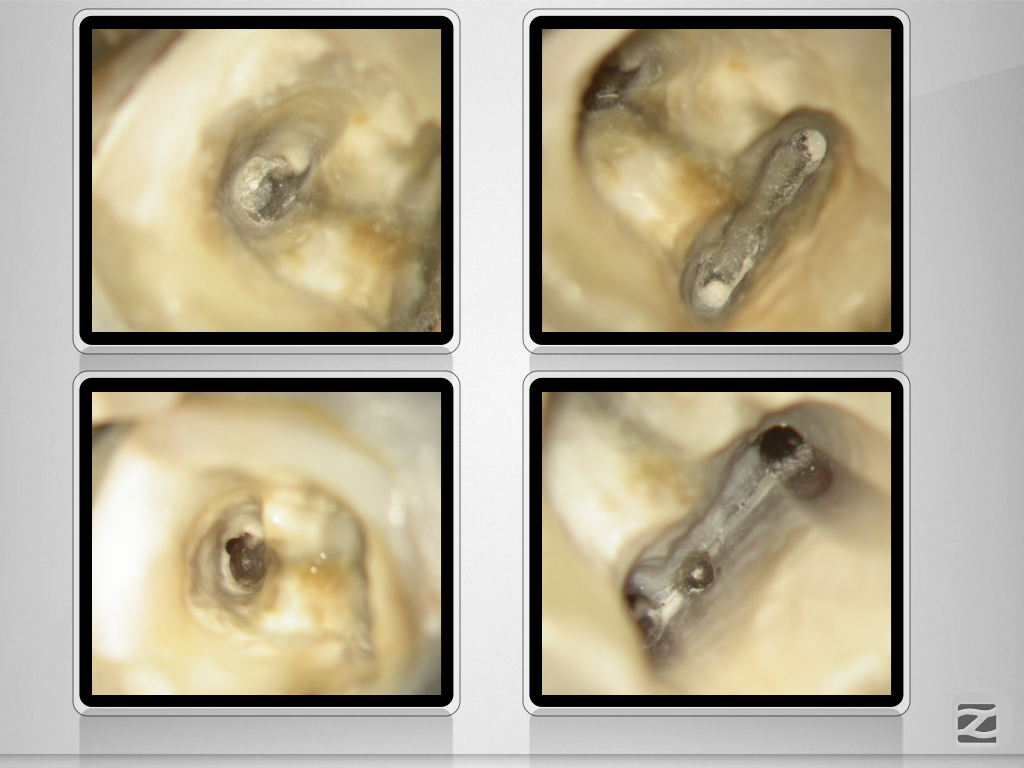

36D.007 Veröffentlicht 29. November 2020 am 1024 × 768 in Wissen was kommt und trotzdem Grenzen erfahren.